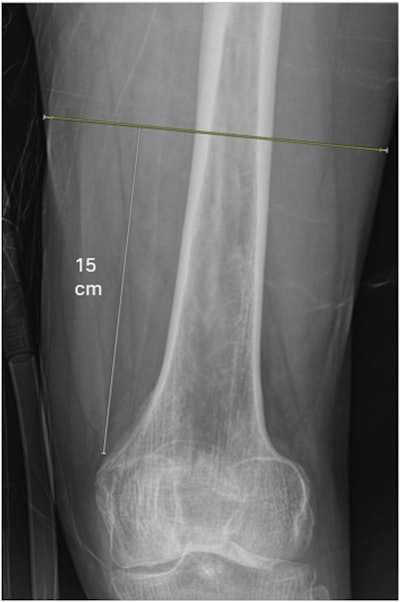

The group gathered data from 199 patients (median age, 85; 68% women) who underwent x-rays during emergency department visits for fractures between 2018 and 2020 and before surgery. The x-rays displayed the distal-and-middle femur, with two musculoskeletal radiology fellows subsequently measuring thigh muscle diameter and soft tissue size using standardized anatomical landmarks.

Example of how thigh muscle diameter measurements were obtained from the anteroposterior radiograph. Diameter of thigh muscle (yellow line) and diameter of whole soft tissue envelope (yellow + white lines) were measured 15 cm proximal to the adductor tubercle.JBJS Open Access

After adjusting for such factors as age, sex, smoking status, preinjury living situation, frailty, and body mass index, the analysis showed that a greater diameter of thigh muscle was associated with significantly lower odds of one-year mortality (odds ratio, 0.74; p = 0.028). This corresponded to an average 26% reduction in odds of one-year mortality for each centimeter increase in thigh muscle diameter, the researchers reported.